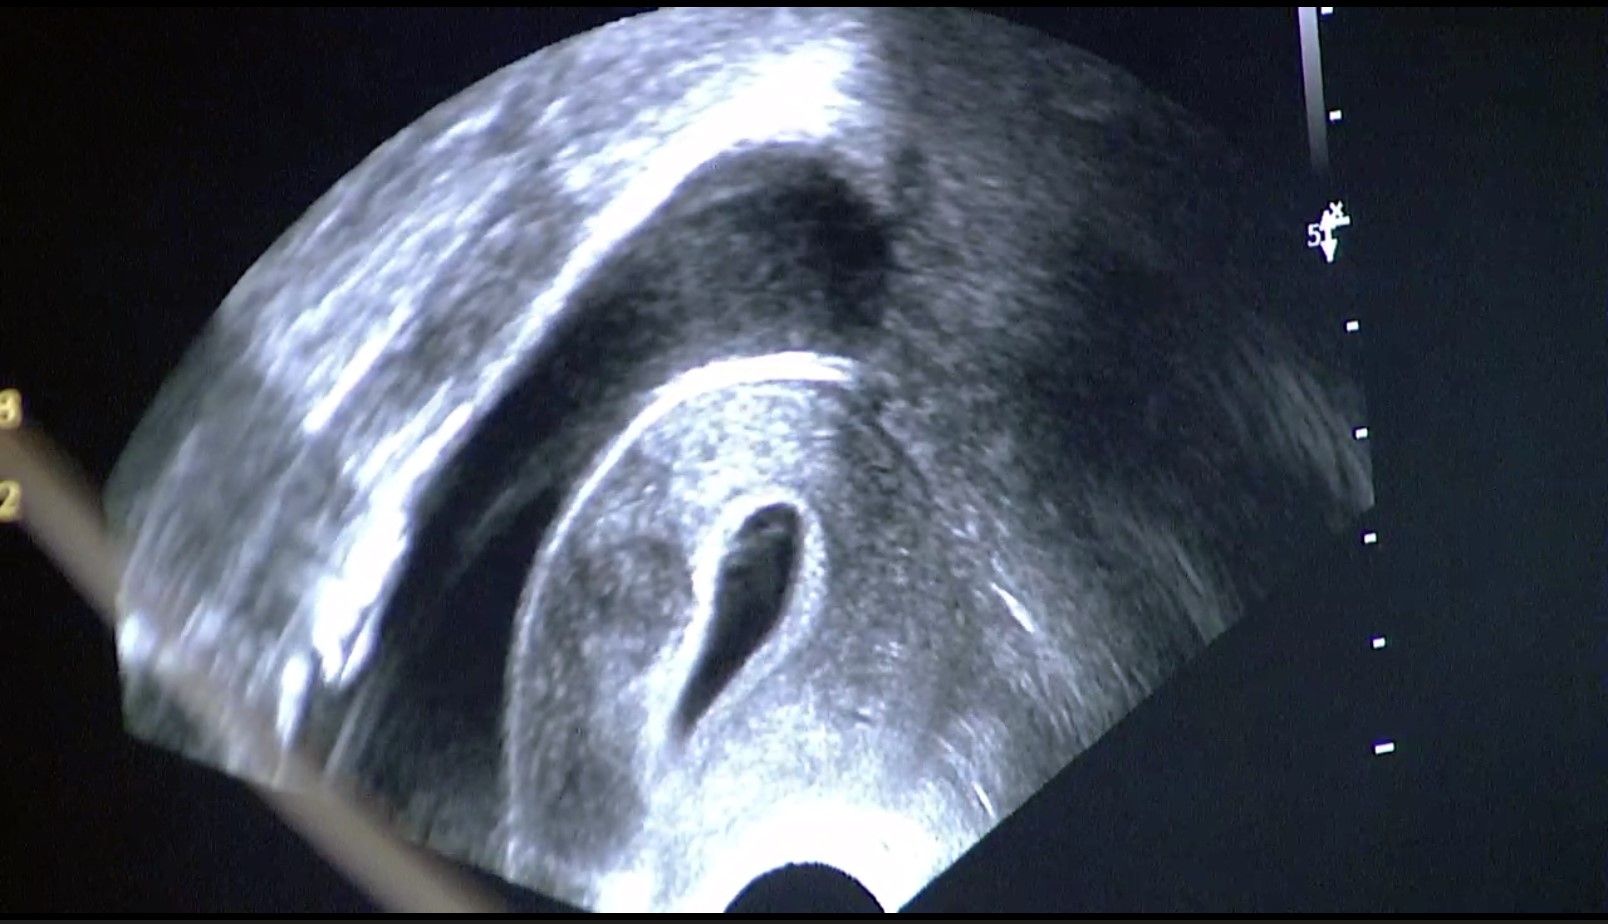

In Tübingen gehen wir mit den neuesten Entwicklungen der Medizin. So bieten wir auch die transzervikale Radiofrequenzablation (Sonata®) zur Myomverkleinerung an. Bei dieser Technik wird durch Einbringen einer speziellen Sonde durch den Gebärmutterhals das Myom per Ultraschall dargestellt und gezielt mit einer speziellen Elektrode punktiert. Über diese Elektrode wird mittels Strom Hitze erzeugt, die das Myom nachhaltig zerstört. Das geschädigte Myom wird in den folgenden Monaten vom Körper abgebaut und damit kleiner.

Geeignet für diese Therapie sind Myome die in der Gebärmutterhöhle und in der Muskulatur liegen (Typ 1, 2, 3, 4, 5, 2-5 und 6).